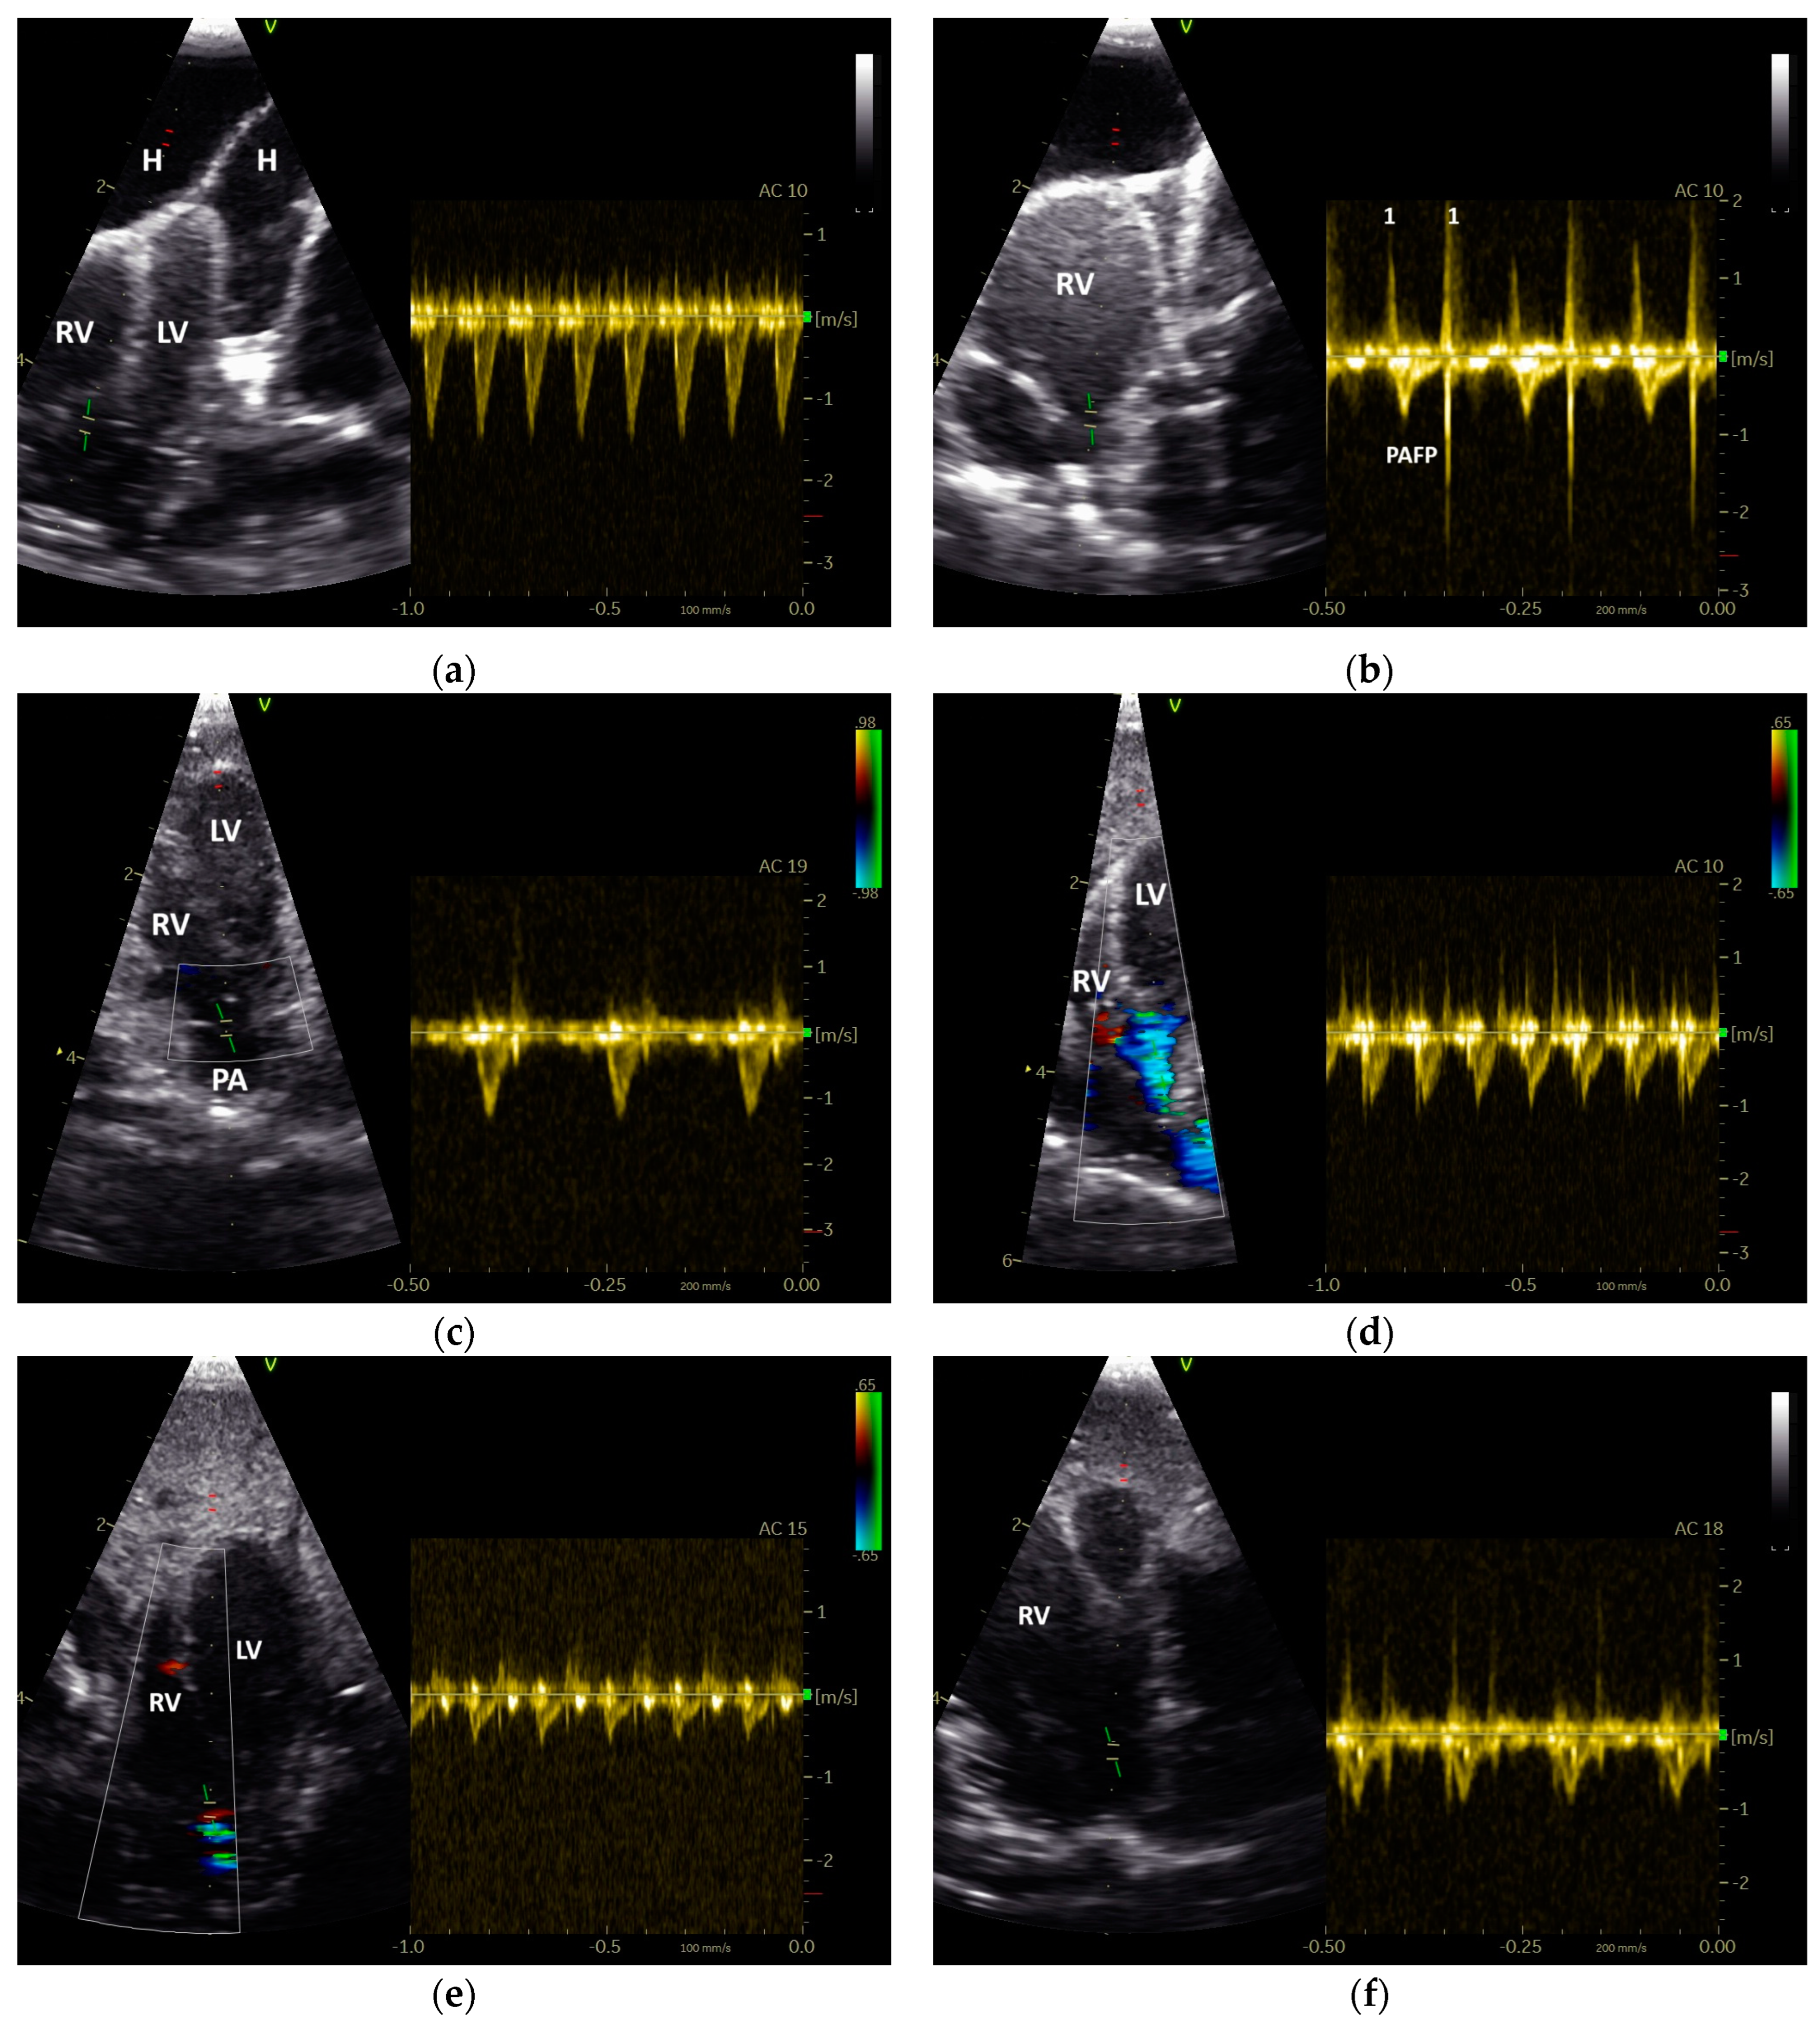

3.1. Shape of PAFP and AOFP of Grey Parrots

3.2. The Influence of Heart Failure on the Shape of the PAFP and AOFP